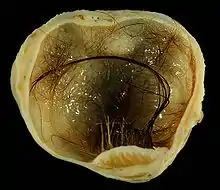

| A small (4 cm) dermoid cyst of an ovary, discovered during a C-section | |

A dermoid cyst is a teratoma of a cystic nature that contains an array of developmentally mature, solid tissues. It frequently consists of skin, hair follicles, and sweat glands, while other commonly found components include clumps of long hair, pockets of sebum, blood, fat, bone, nail, teeth, eyes, cartilage, and thyroid tissue.